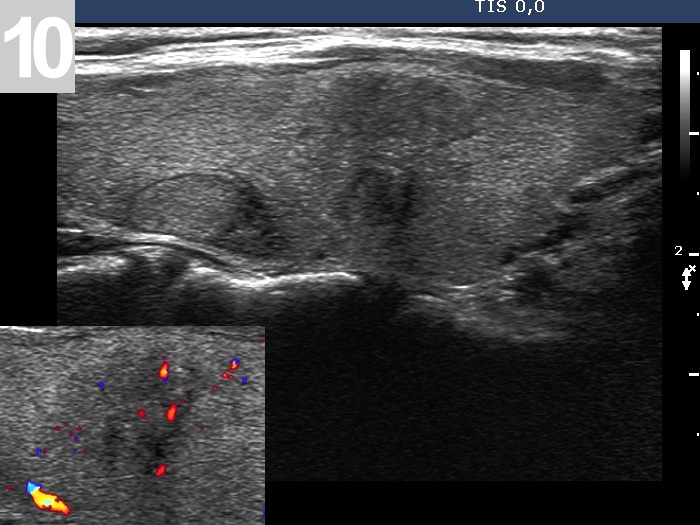

3 US of thyroid cancer

Pre- and postoperative ultrasound in thyroid cancers

Cases to be discussed on January 18, 2024